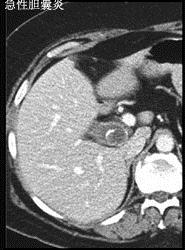

问题 有关急性胆囊炎哪项是错误 ( )

选项 A、一般无寒战 B、黄疸出现早而明显 C、右上腹可有压痛、肌紧张 D、胆囊区深吸气时有触痛反应 E、有时可扪及有触痛的肿大胆囊

答案 B